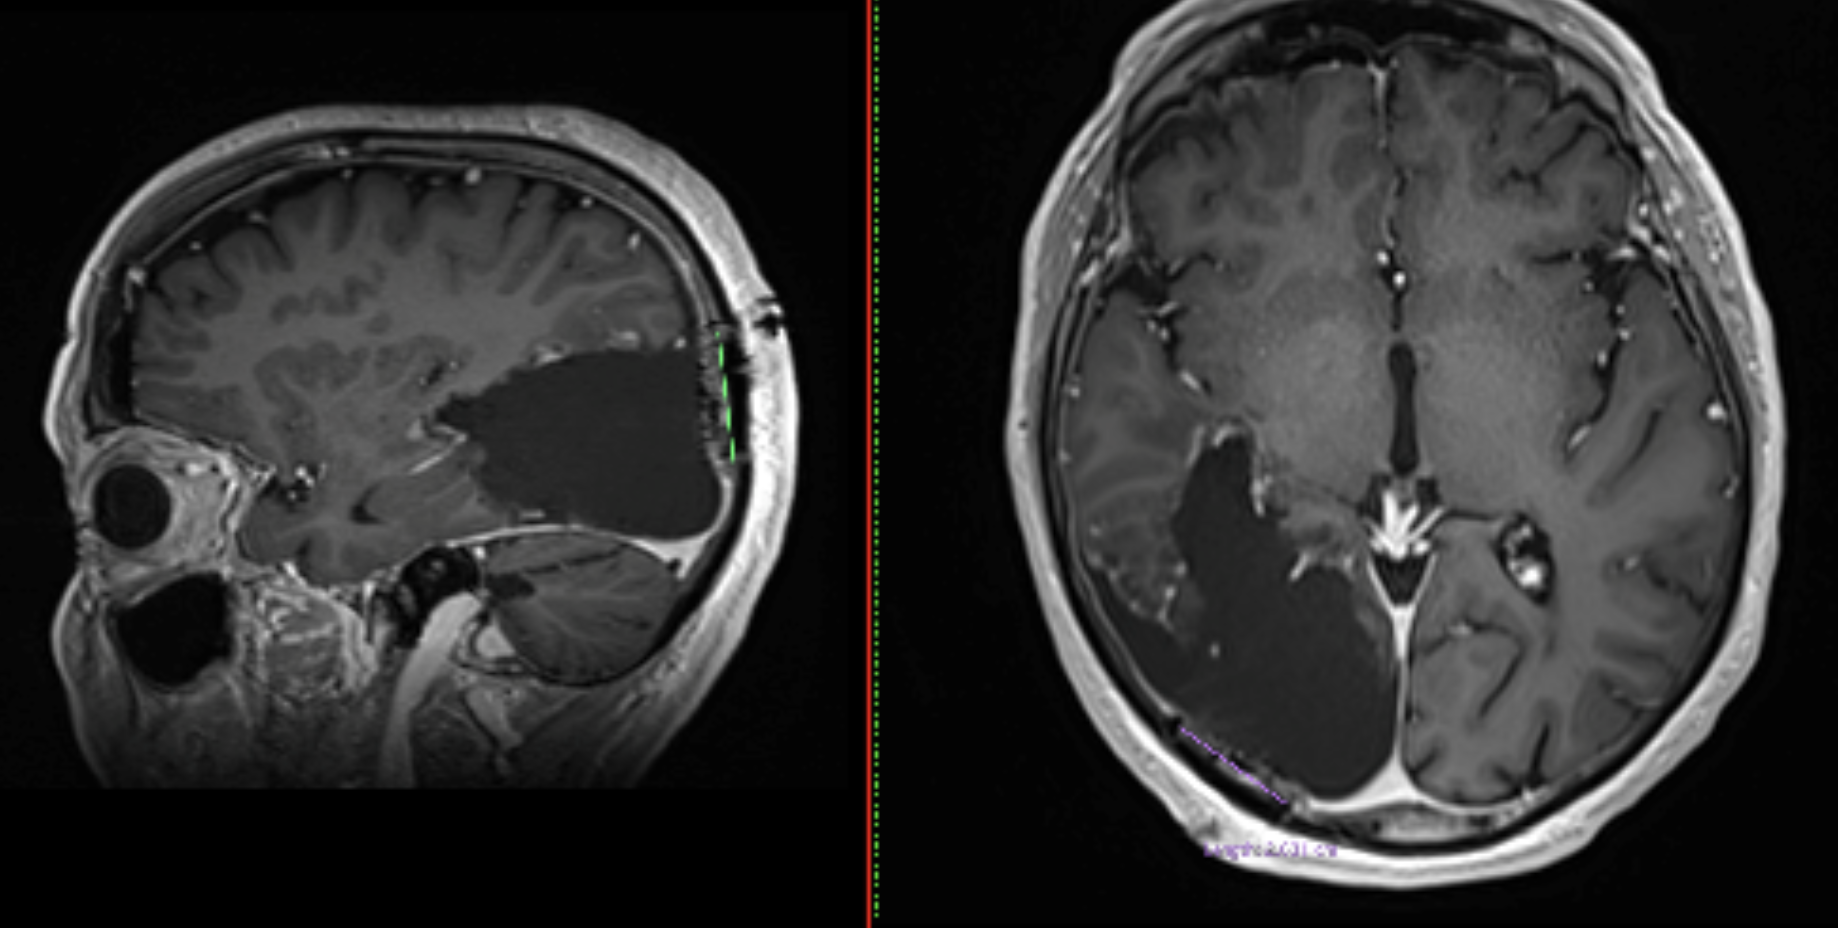

- RMN cerebral cu substanță de contrast

- Imagistică avansată

- toate investigațiile imagistice disponibile (RMN, CT, angiografie, dacă este cazul)